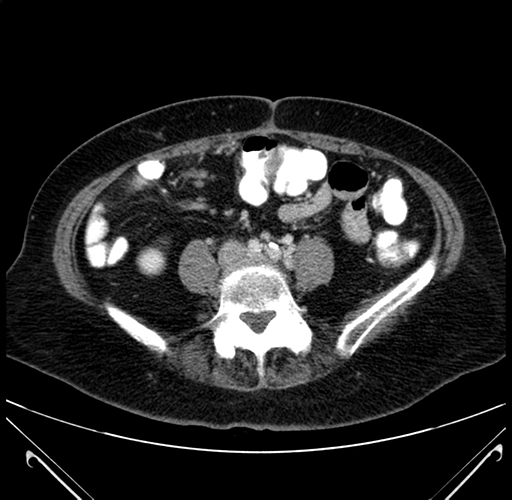

Axial Venous